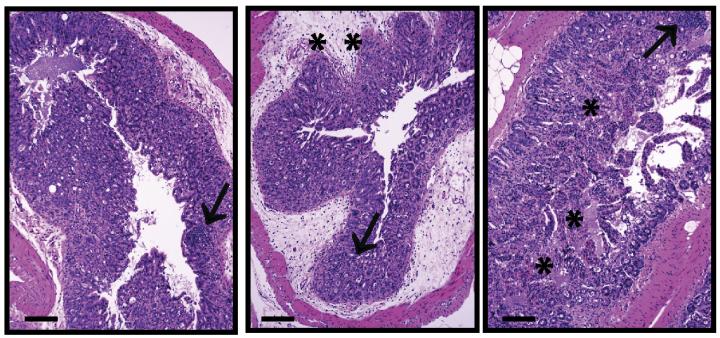

Packing on the pounds may lead to dangerous inflammation in response to anti-cancer treatment, according to a study by William Murphy and colleages at UC Davis. The study, published in The Journal of Experimental Medicine , shows that overweight mice develop lethal inflammation in response to certain anti-cancer therapies, suggesting a possible link between body weight and adverse side effects in cancer patients treated with similar protocols.

Cancer treatment has been revolutionized by new approaches aimed at stimulating the body's own immune system to fight off tumor cells. These "immunotherapy" approaches have proven successful in many types of cancer, but they are also associated with dangerous inflammation in some patients. This group had previously shown that treating mice with a combination of immune-activating stimuli—anti-CD40 antibodies and interleukin (IL)-2—stimulates tumor-fighting immune cells to eradicate cancer in young mice. In old mice, however, the same treatment triggered deadly inflammation.

As with humans, mice often accumulate fat as they age. Murphy's group now finds that lethal inflammation in response to anti-CD40/IL-2 immunotherapy is determined more by fat than age. Like old mice, young, obese mice succumbed to lethal inflammation in response to treatment. And putting older mice on diets protected them. This suggests that the results of preclinical immunotherapy studies in mice and humans—primarily performed on young subjects—should be interpreted with caution, particularly as cancer is a disease that predominately affects the elderly.